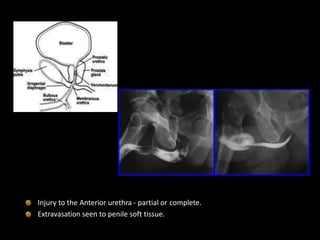

Injury to the Anterior urethra - partial or complete.

Extravasation seen to penile soft tissue.